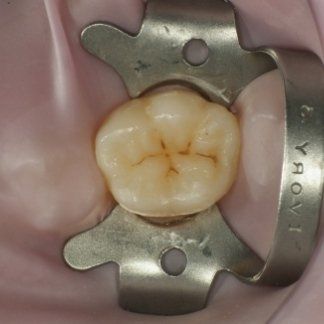

Sealing teeth is the practice of placing a "varnish", usually white in colour, on the grooves of permanent molars to

protect them from decay. If applied correctly, this procedure is extremely effective and long-lasting.

Sealants are applied to permanent teeth (usually the first and second molars) around the age of 7-8 for the first molars, and 12-13 for the second molars.

However, this practice is often carried out inconsiderately. Not all teeth need to be sealed: the morphology (i.e., shape) of the teeth, the caries susceptibility of the child, and oral hygiene at home need to be evaluated. If, based on these considerations, sealing is deemed necessary, it should be conducted according to a precise clinical protocol, which includes the application of a rubber dam (see topic in "Services"), cleaning of any pigmented grooves, and bonding of the sealant. "Forgetting" one of these steps results in poor-quality therapy: for example, sealing grooves without prior cleaning risks sealing decay underneath. Upon inspection by the dentist, these grooves would appear sealed... but so would the underlying decay, which wasn't removed, making it invisible. This would result in dental decay that cannot be diagnosed in its early stages as it is "covered" by the dental sealant... truly not a good job! Below are examples of correctly sealed and emblematic cases of how sealing should NOT be performed.